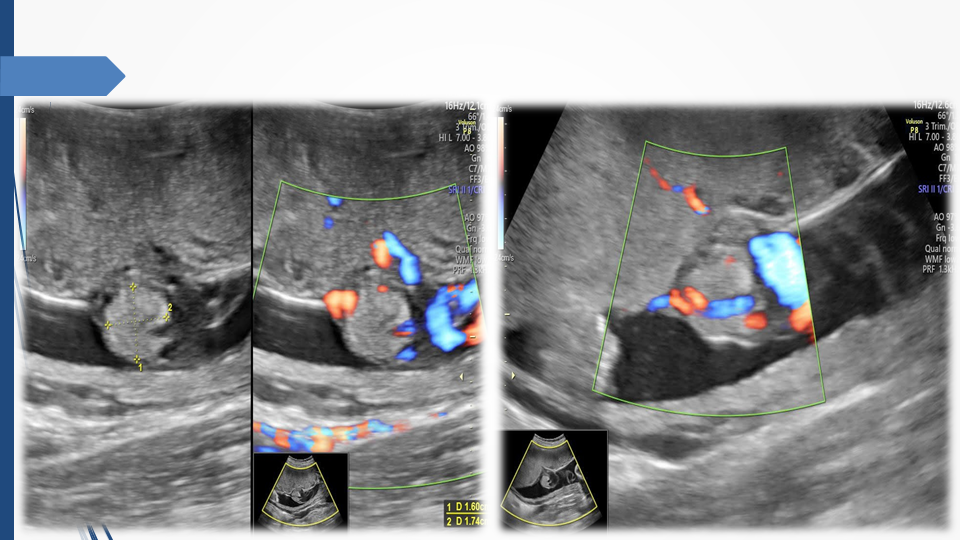

Tầm soát chủ động bất thường dây rốn và tuần hoàn thai để giảm thiểu nguy cơ thai lưu đột ngột - Báo cáo loạt ca hiếm gặp và khuyến nghị thực hành